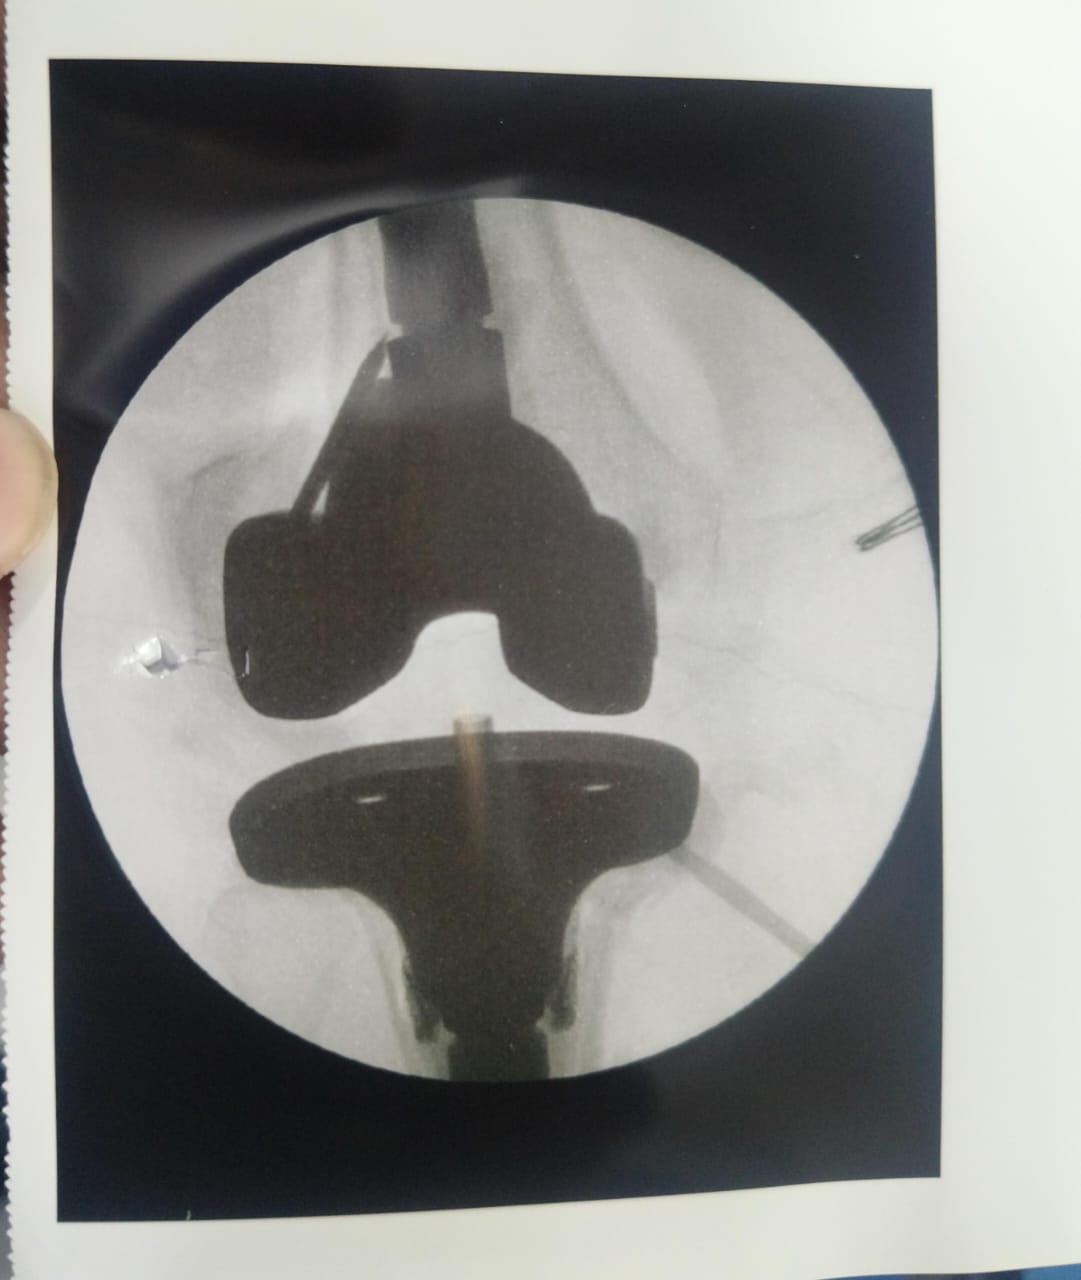

Dr Ajay Randive : IS MS Ortho (Mumbai) MRCSI ( UK) Consultant knee, Hip ,& Spine Surgeon, Dr Ajay Randhive is a eminent Knee, Hip , & Spine Surgeon practicing in to areas Andheri East,Santacruz East. Dr Ajay Randive did his MS Ortho residency from LTMMC, Sion Hospital Mumbai. He did overseas training in UK from 2003 till 2008. He is trained in total Knee Replacement, Hip Replacement, Revision Hip Replacement And Revision Knee Replacement Surgeries. He has worked at The Royal London Hospital. IN London where he worked a clinical fellow in joint Replacement unit. He has carried out more than 5000 Knee Replacement surgeries, 2500 Hip Replacement Surgeries, More Than 500 Revison Knee And Hip Replacement Surgeries 600 Spine surgeries & more than 1500 arthroscopic surgeries (Knee & Shoulder).